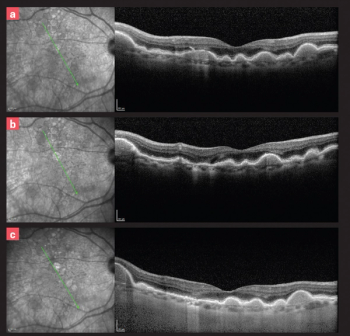

Trace the path of diabetic retinopathy disease via images.